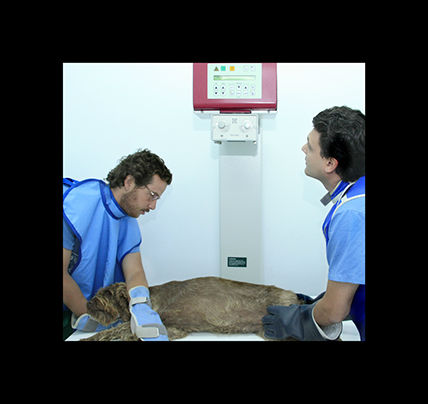

radiología

La radiologia es imprescindible en traumatologia y en algunos diagnosticos, ya sea mediante radiologia simple ó de contraste.